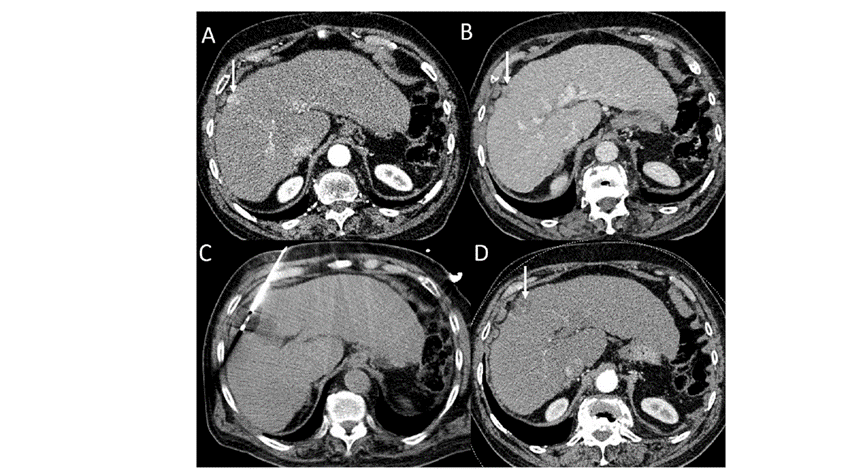

(A)動脈期CT圖像顯示有一個包膜下結節(jié)(箭頭)。(B)門靜脈期CT圖像顯示病灶區(qū)(箭頭)。(C) 在手術過程中的CT顯示一個冷凍探針位于病灶內。患者在手術及住院期間無并發(fā)癥及重大并發(fā)癥發(fā)生。隨訪時間中位數為7個月(范圍:3-12個月),隨訪期間患者無局部腫瘤進展或死亡。

(A)門靜脈期 CT 圖像顯示膽囊附近有病變(箭頭)。(D)消融手術后 1 個月CT 顯示完全消融。